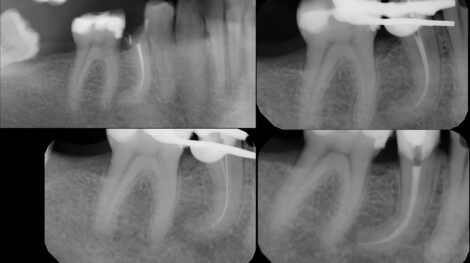

Leczeniem kanałowym zajmuję się od 14 lat i od samego początku była to dziedzina stomatologii paradoksalnie dla mnie najciekawsza. Po roku od ukończeniu studiów, aż do dnia dzisiejszego leczenie kanałowe stanowi 90% mojego czasu pracy.

Tak duża ilość przypadków od najprostszych do ekstremalnie skomplikowanych pozwoliła mi przeprowadzać zabiegi w sposób przewidywalny, sprawny i z minimalnym ryzykiem powikłań.